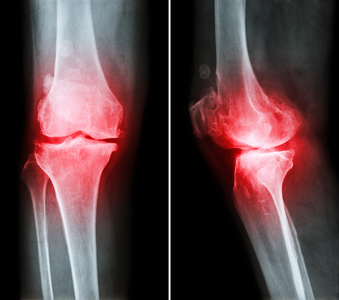

临床中,常见的关节炎可分为骨关节炎、类风湿关节炎、风湿性关节炎、痛风性关节炎、感染性关节炎等五类。

第一类骨关节炎

部分病人在早期的主要临床表现是关节肿胀,上下楼梯疼痛、受限等;疾病晚期可出现关节畸形,行走疼痛、肌肉萎缩等症状。

第二类类风湿关节炎

类风湿关节炎,是一种病因未明的全身免疫性疾病,不但影响着关节功能,还会影响其他器官。

手、足等小关节的对称性、侵袭性病变,绝大多数患者伴有晨僵。目前该病确诊尚依赖于血清学检查。该疾病具有较高的致残率,严重影响生活。一旦确诊,需要终身治疗,通过正规治疗后,绝大部分患者病情可得到有效控制。

第三类风湿性关节炎

风湿性关节炎是一种常见的急性或慢性结缔组织炎症,此处的风湿性关节炎与我们平时常说的“风湿病”是截然不同的,并非中医中的“风湿病”。

风湿性关节炎以关节和肌肉游走性酸痛、红肿为特征。与A组乙型溶血性链球菌感染密切相关,寒冷、潮湿等均可诱发本病。

与类风湿关节炎的小关节为主要病变不同,该病临床以下肢大关节如膝关节、踝关节最常受累。由于风湿热活动期以累及关节和心脏为主,因此风湿性关节炎患者常伴有心肌炎、心内膜炎、心包炎等。